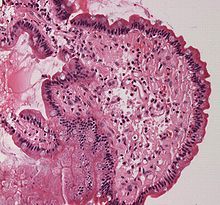

3.確診就是要證實在組織間隙中有澱粉樣蛋白的沉積,最可靠的方法是從病變組織做活檢和病理切片檢查。